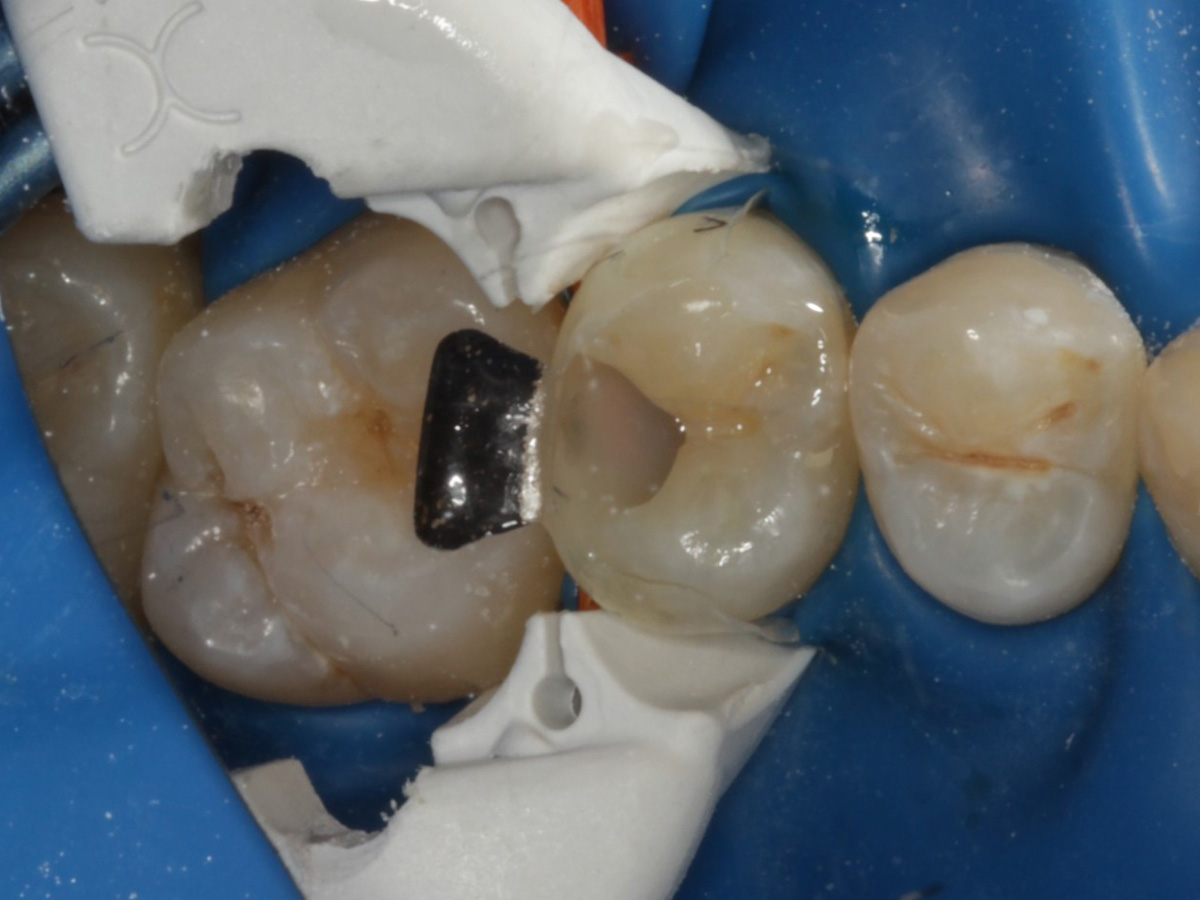

Abbildung 1

Approximalraumkaries an Zahn 25 distal

Abbildung 4

Schutz des Nachbarzahnes und des Kofferdams mit wiederverwandter Bioclear Biofit Matrize (gereinigt und sterilisiert); Separation zur Applikation der Matrize mit Heidemannspatel

Abbildung 5

Defektdarstellung